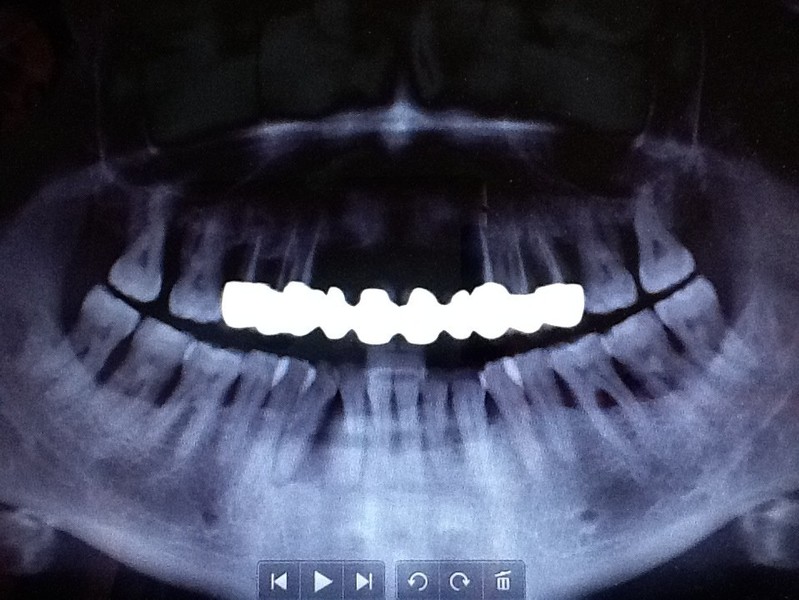

IMPLANTOLOGIA A CARICO IMMEDIATO.RIPRISTINO ESTETICO E FUNZIONALE IN 24h

RIABILITA LA TUA BOCCA IN 2 GIORNI!

Impianti dentali faccette estetiche e denti fissi! guarda questo caso eseguito in 2 giorni